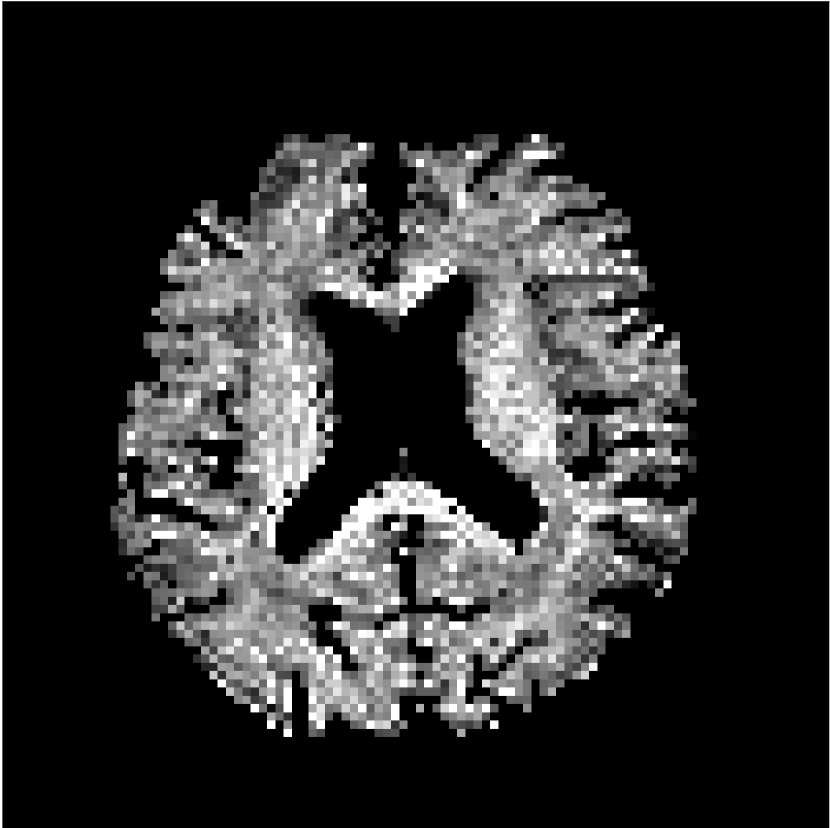

Figure 8 shows examples of non-diffusion-weighted images before and after processing. The raw images (Raw) served as the input for the magnitude deep learning (MCNN) and complex deep learning (CCNN) methods.

Raw

MCNN,

MCNN Resid.,

CCNN,

CCNN Resid.,

No PF

5/8 PF

Both methods remove artifacts, but the MCNN method allows residual rippling artifacts to pass through in the presence of partial Fourier. These rippling artifacts are not present in the CCNN method.